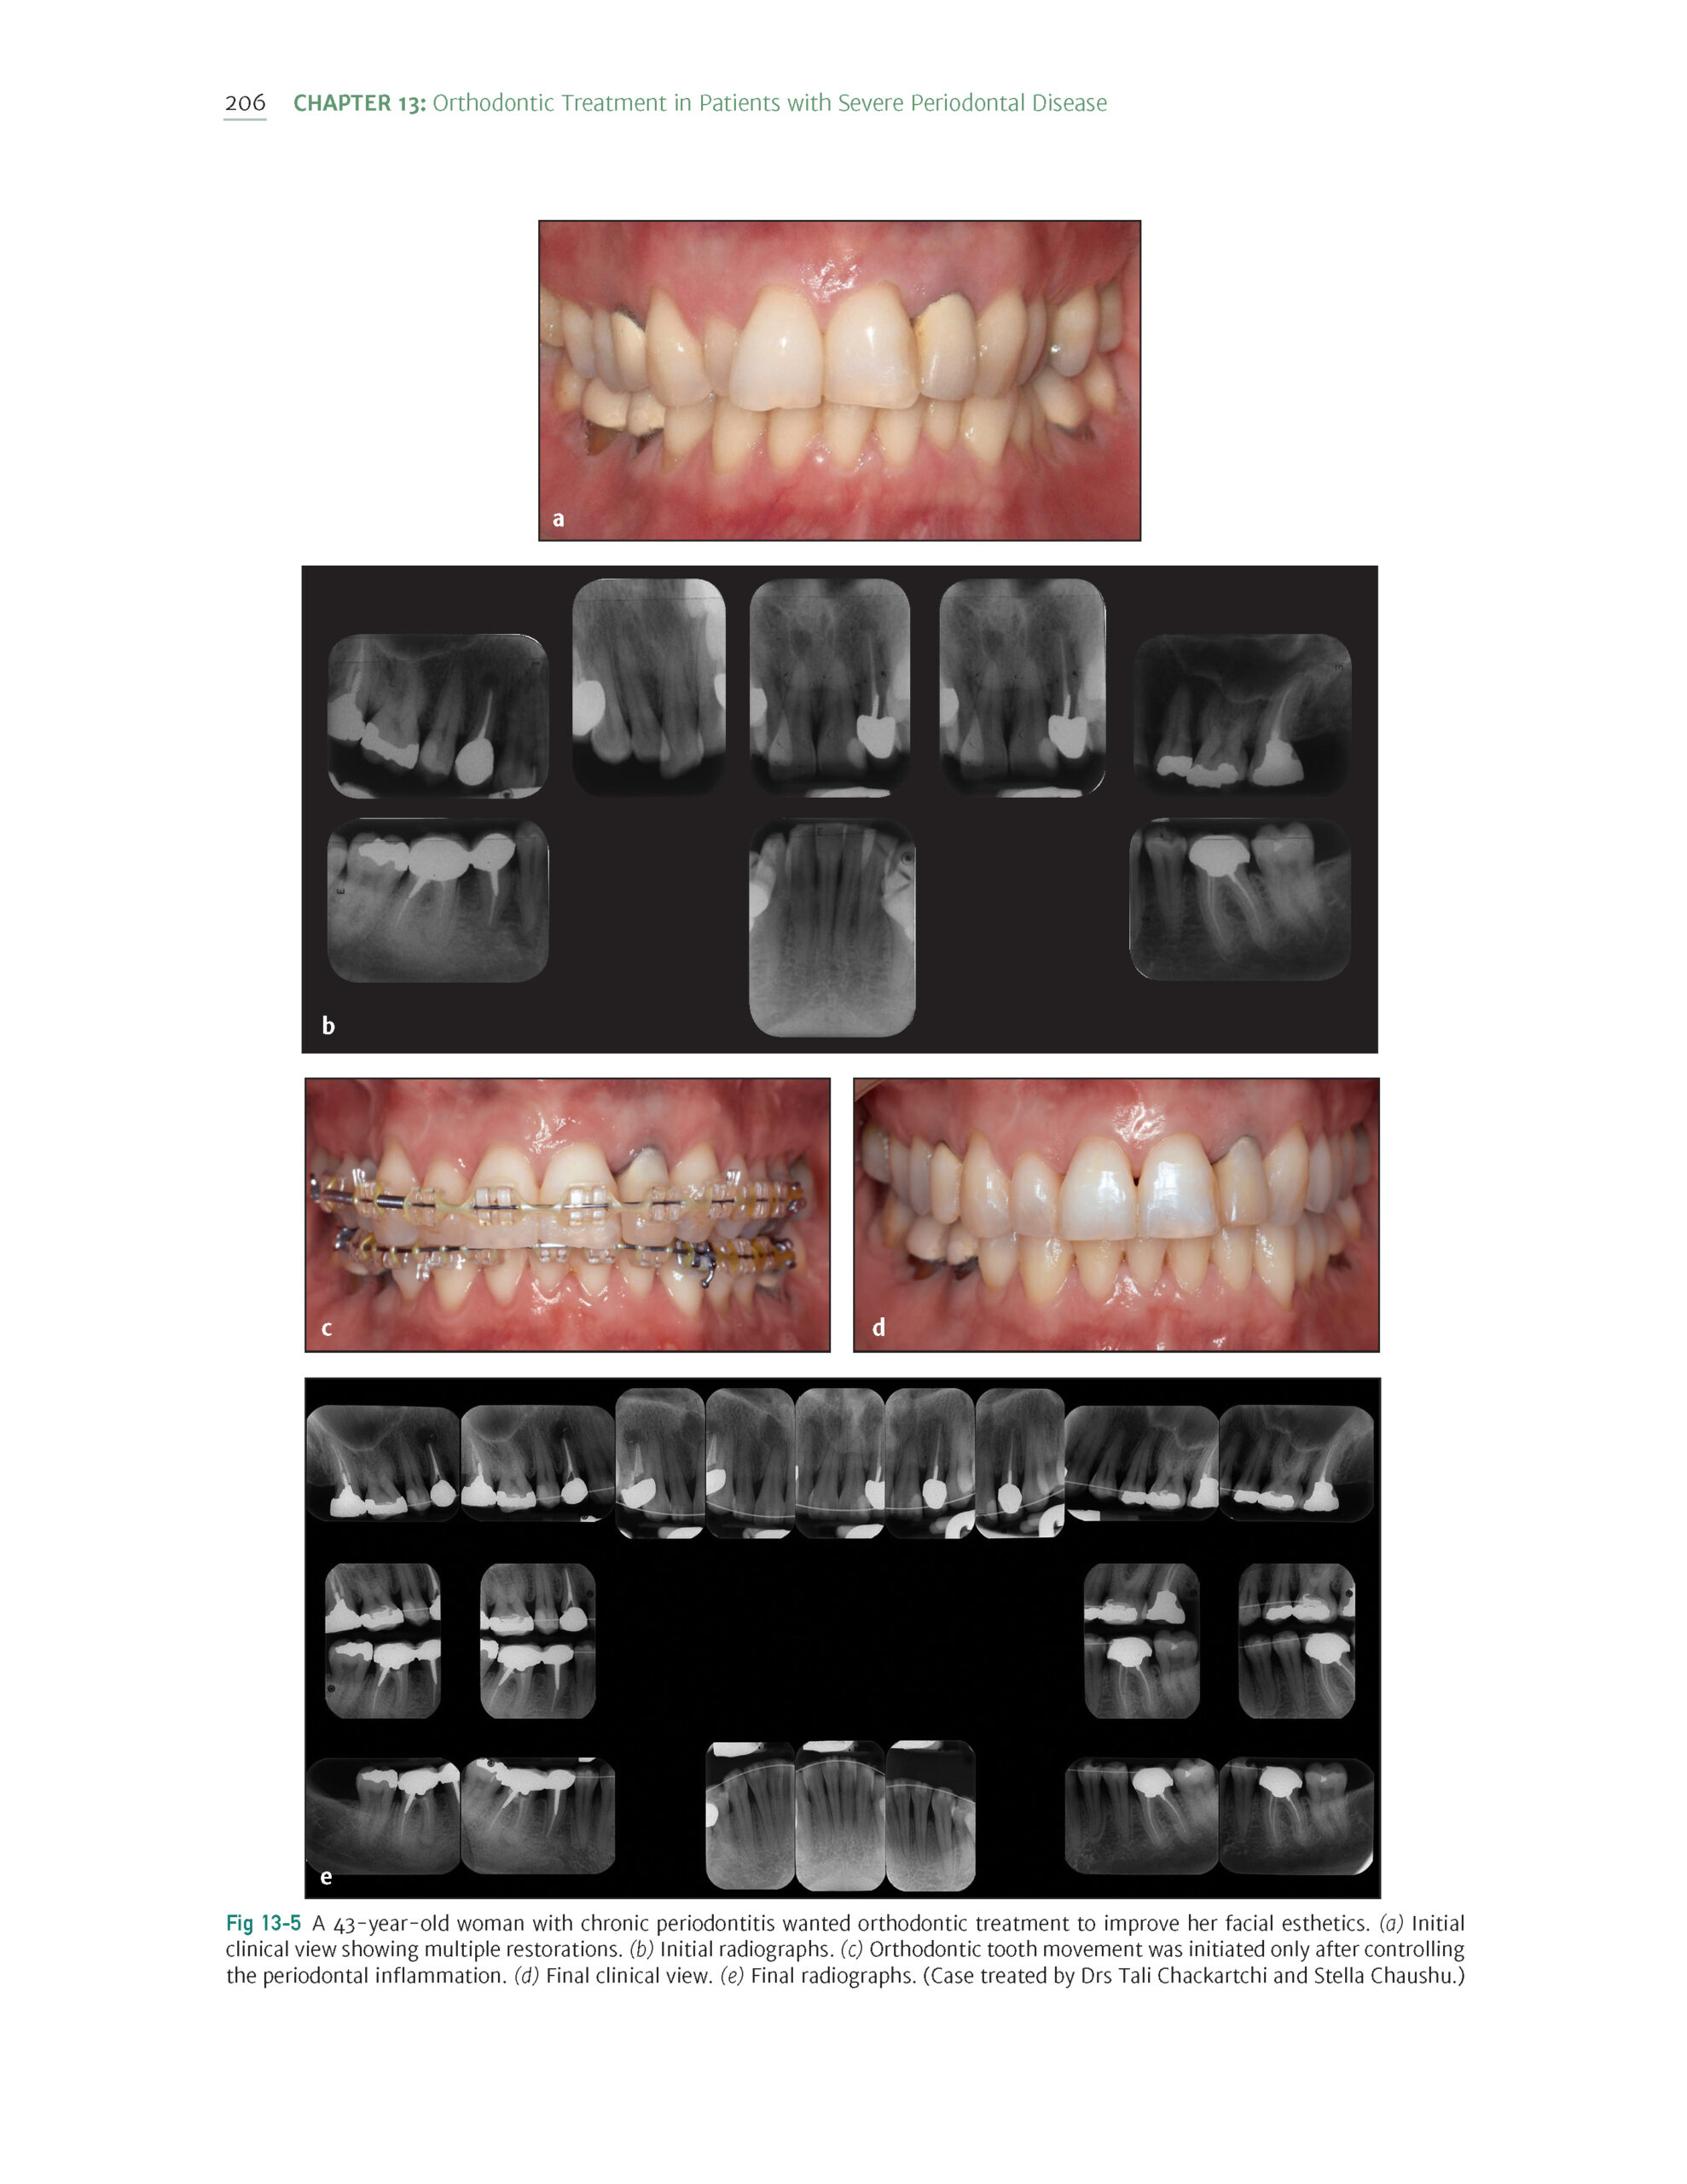

The Ortho-Perio Patient: Clinical Evidence and Therapeutic Guidelines 2019